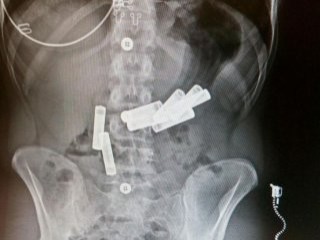

Düzce Üniversitesi Araştırma ve Uygulama Hastanesi'nde tedaviye alınan K.A.'nın röntgeni çekildi.

Doktorlar, psikolojik sorunları olan genç kızın karnındaki pilleri görünce şaşırdı. Röngende vücudunda 8 kalem pil olduğu görülen K.A.'nın tedavisi devam ediyor.